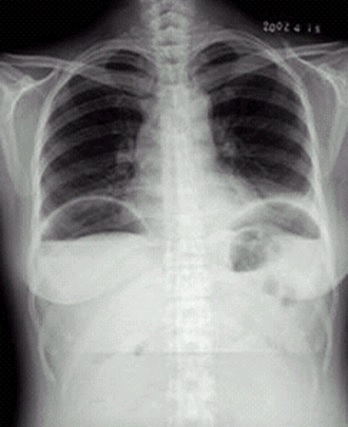

04卷-3.病史:男性,53岁,咳嗽、体重减轻4个月。诊断(本题满分2.00分)

A.左下肺炎

B.左下包裹性积液

C.左下肺癌

D.左下肺结核

本题答案:C

题目解析:

【该题针对“X线-肺癌”知识点进行考核】